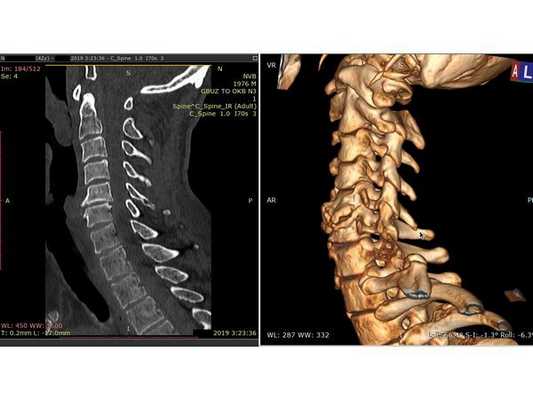

По результатам КТ шейного отдела позвоночника травматической патологии не выявлено, отмечается сглаженность шейного лордоза, спондилёз (естественное изнашивание и старение позвонков с формированием нежелательных костных разрастаний), наиболее выраженный в позвонках C5-C6. МРТ исследование по техническим причинам выполнено на следующий день: выявлен стеноз (сужение) позвоночного канала с уровня C3-C4 до уровня C5-С6 с формированием очагов миелопатии (поражения спинного мозга) с уровня C3 до C6; отмечается "свечение" тела С5 позвонка, свидетельствующее о наличии гемокомпонента в ячейках губчатой костной ткани. Предположительно, гемокомпонент появился вследствие компрессии тела С5 позвонка в момент травмы.

МРТ шейного отдела позвоночника: в Т2-режиме видны миелопатические очаги в сегменте С3-С6 на фоне абсолютного стеноза с уровня С3-С4 до С5-С6

Резкое сгибание-разгибание шейного отдела позвоночника на фоне существующего дегенеративного стеноза позвоночного канала на шейном уровне привело к кратковременному сдавлению и ушибу спинного мозга между задней продольной связкой и жёлтой связкой. В итоге сформировались миелопатические очаги на данном уровне. При этом на КТ травматической патологии не выявлено, но отмечены выраженные спондилёзные изменения в сегменте С5-С6, которые свидетельствовали о том, что имелась нестабильность на данном уровне, приведшая по механизму саногенеза (выздоровления) к выраженному разрастанию остеофитов и формированию костного блока. Следствием такого саногенетичного процесса стало формирование вторичного стеноза. На МРТ снимке отмечается "свечение" тела С5 позвонка, по которому можно предположить, что в момент травмы было компрессионное воздействие на тело С5, не приведшее к необратимой деформации костных структур. В общем, сформировавшийся у пациента костный блок "выдержал". Тем не менее травма спинного мозга на шейном уровне произошла, что повлекло функционально значимую неврологическую симптоматику. На фоне консервативного лечения антиагрегантными, противовоспалительными, глюкокортикостероидными и нейротропными препаратами получена быстрая положительная динамика. Можно сказать, что пациенту "повезло". Подобные случаи достаточно редки. Обычно травма спинного мозга происходит на фоне разрушения позвонков, так называемая осложнённая травма позвоночника. У этого пациента травма спинного мозга произошла при целых позвонках, хотя на МРТ видно, что компрессия тела С5 позвонка имела место быть.